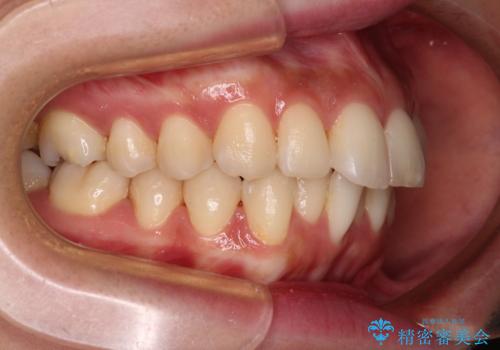

- 口元の閉じにくさを気にして来院された患者様です。

上下ともに歯列が前方に突出していたため、上下左右の第一小臼歯4本を抜去し、ワイヤー装置による矯正治療を行うこととしました。